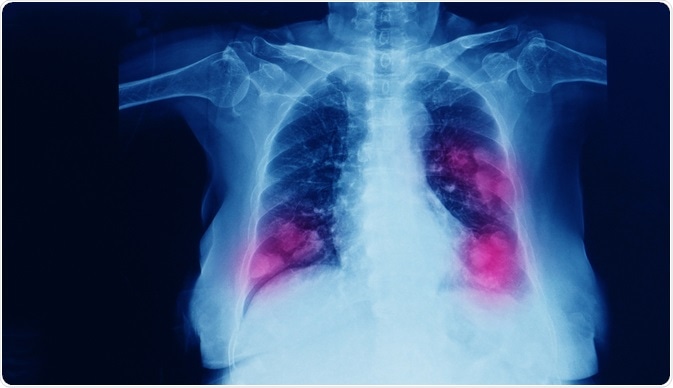

Metastatic Lung Cancer

Image Credit: Yok_onepiece/Shutterstock.com